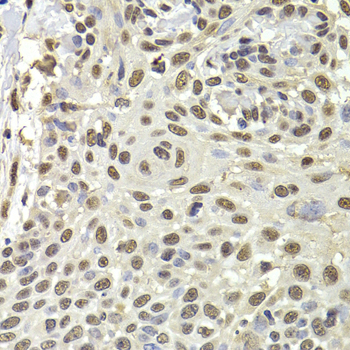

Immunohistochemistry of paraffin-embedded human well-differentiated squamous skin carcinoma using PUF60 antibody at dilution of 1:100 (x400 lens).